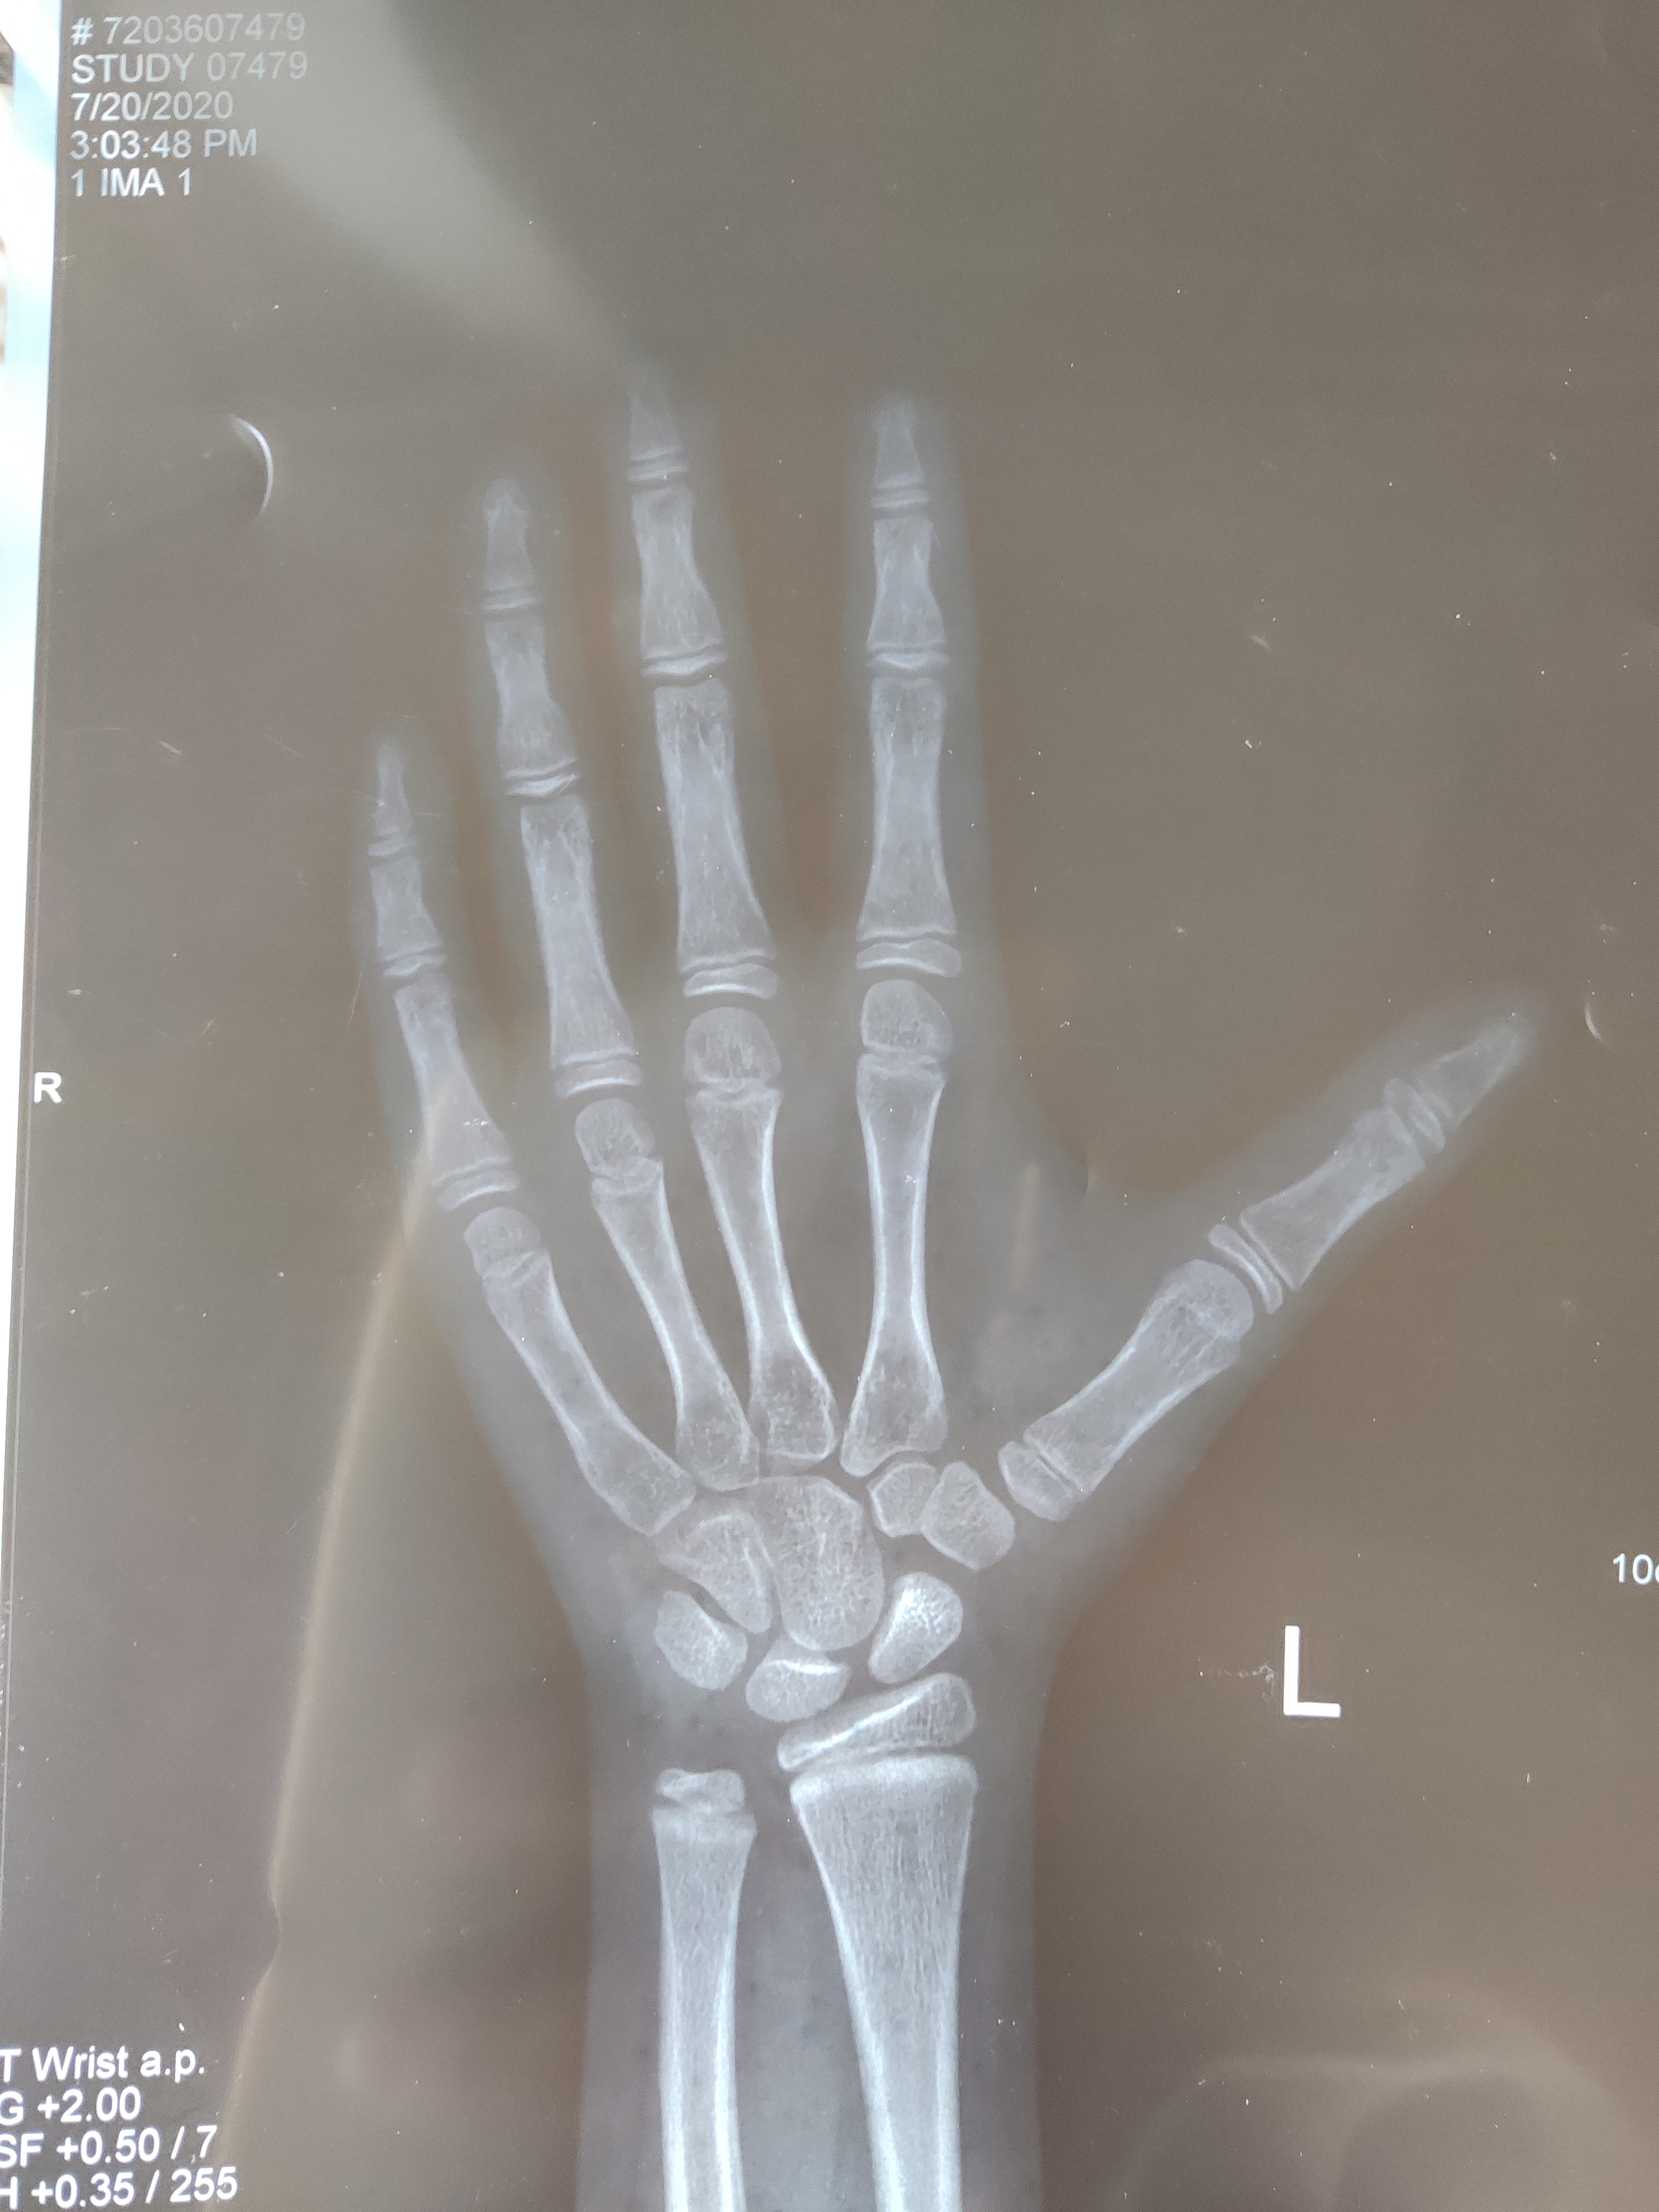

我觉得不对劲,把孩子拉过来看了看,果不其然,孩子已经进入青春期,*丸睾**也开始发育了,他现在这种情况,骨龄肯定是比年龄大的,所以马上建议家长带着孩子去拍个骨龄片,确定一下骨龄大小。

前几天妈妈拿着片子来复诊,我用中华05给孩子评估,果不其然,孩子骨龄已经11.9岁了,比年龄大了将近2岁。按照骨龄来评估,孩子目前身高在10百分位,按照这个生长曲线,孩子成年终身高很可能在165左右,妈妈当时就说不出话了,这对她来说,无疑是一个晴天霹雳。